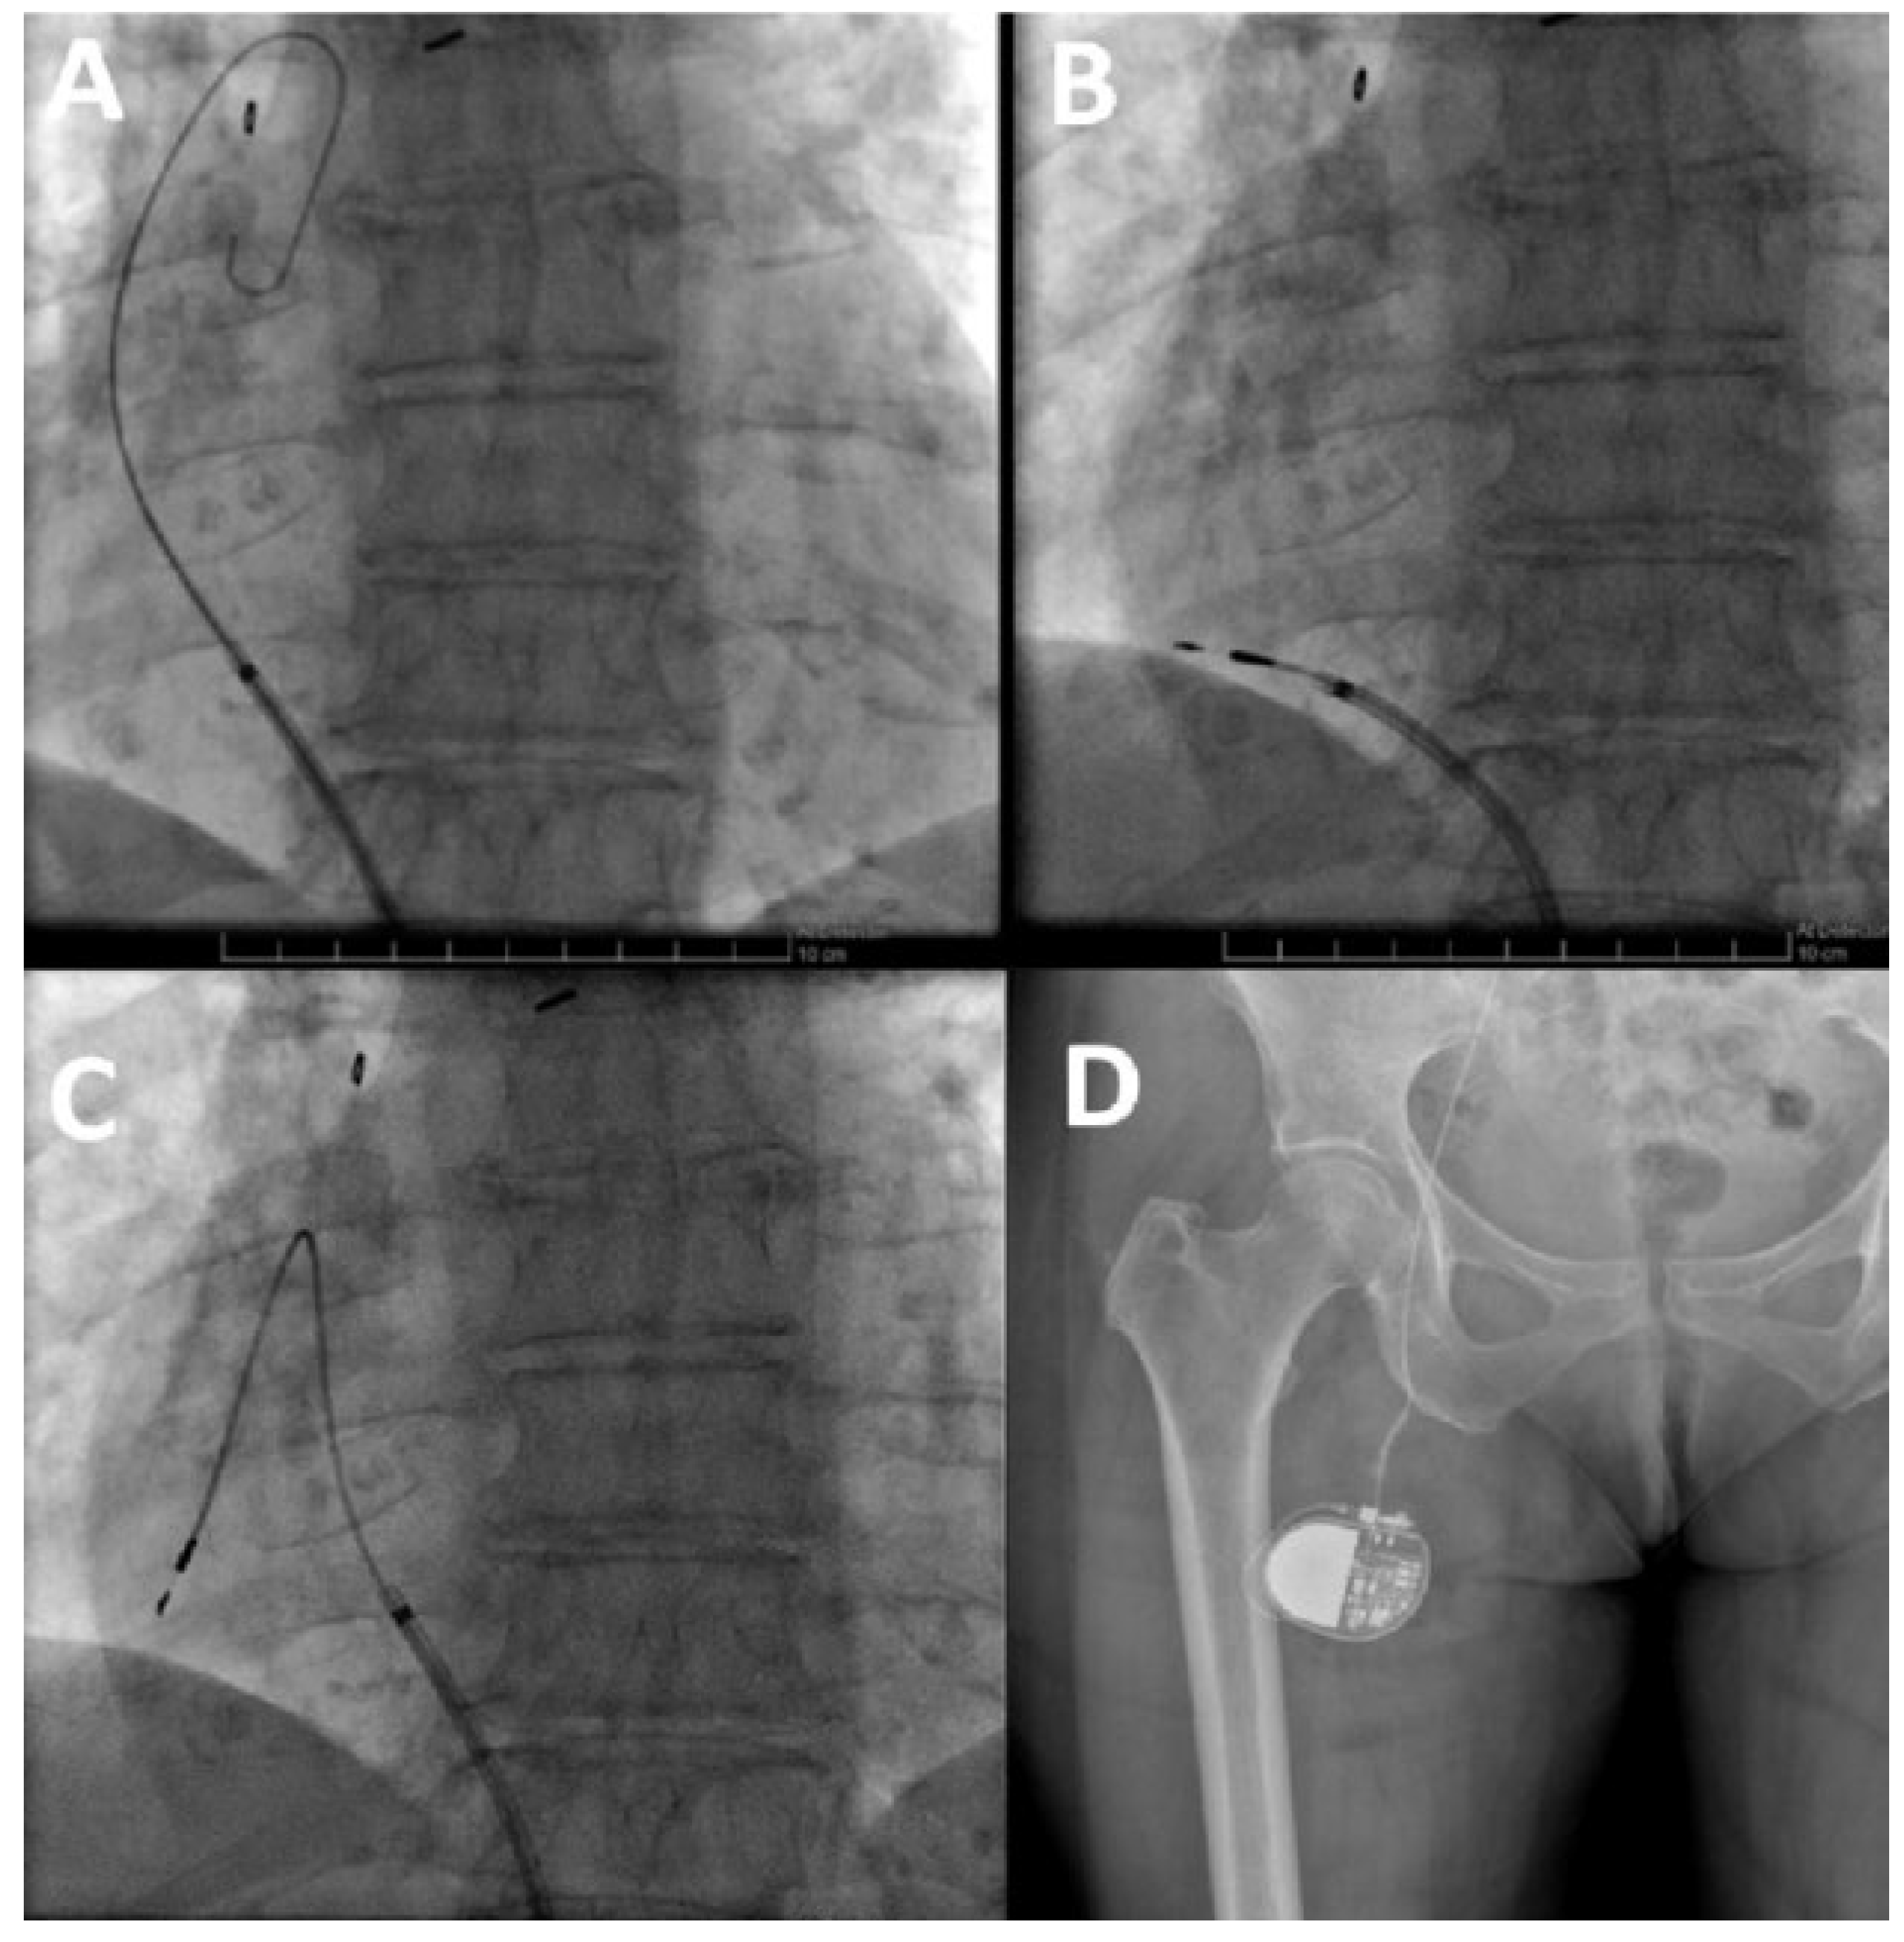

Pacemaker implantation: The right femoral vein was punctured in the groin, approximately 3 cm below the iliac ligament. A deflectable 8.4F guiding catheter (Medtronic® Minneapolis, MN, USA) was advanced over a 0.35 inch guidewire into the right atrium. A 69 cm Medtronic Select Secure 3830 lead was implanted in the right atrial appendage (Figure 2 and Figure 3). This is a 4.1 French lumenless fixed-helix active-fixation pacing lead that requires a guiding catheter for positioning. This model was chosen because of its length (59 cm and 69 cm available), its stability, and its high flexibility and tensile strength to accommodate increased stress due to hip flexion. The electrical parameters were normal and atrial pacing at 130 bpm revealed 1:1 conduction (with normal QRS width). For this reason, and to avoid excess foreign body material, a ventricular lead was not implanted. The lead was connected to a Medtronic Relia SR pacemaker, which was placed in a pocket in the upper anterior thigh. The wound was closed with resorbable subcuticular monofilament suture and a waterproof dressing was applied. The patient was discharged on the day after the procedure, with the device programmed to AAIR 60– 120 bpm. The wound healed well, without any discomfort caused by the generator pocket (Figure 4). The patient had marked symptomatic improvement, with rate histograms showing good adaptation despite the unusual generator location (Figure 5). Follow-up for more than 4 years has been uneventful, with stable electrical parameters.

Figure 2. Device implantation. (A) Deflectable guiding catheter positioned in the right atrium over a guidewire via the right femoral vein. (B) Lead insertion into the right atrium via the guiding catheter. (C) Formation of a loop to allow sufficient slack and stabilise the lead. (D) Generator positioning in the superior and anterior part of the right thigh.